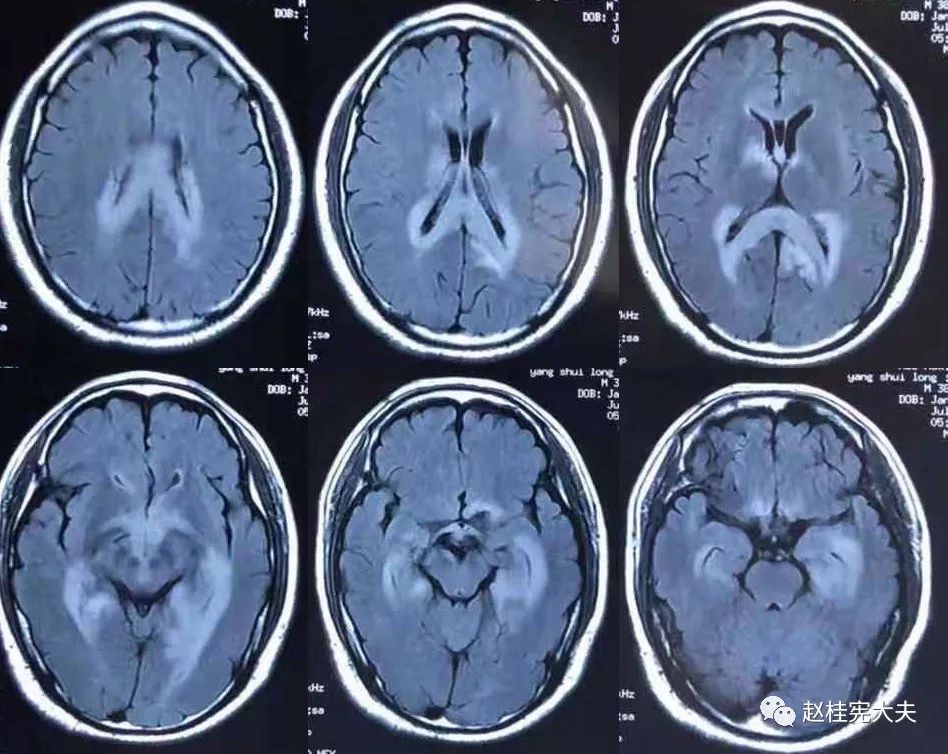

7.20复查头颅MRI平扫:胼胝体、穹隆及双侧脑室旁、基底节区、右侧延髓、桥臂广泛信号异常,对照前片(7.10)范围明显缩小。

2018.10复查头颅MRI:胼胝体压部、左侧部分枕颞叶、侧脑室枕角旁、中脑脱髓鞘病变,视神经脊髓炎谱系病?结合对照前片(7.4)病变范围有所缩小。

我看到患者时的思考:当了解了患者前期诊疗经过后,在看到患者磁共振片子时,我的第一反应就是淋巴瘤。尽管患者激素治疗后症状有好转,病灶在磁共振上看起来也是有好转,但淋巴瘤也会出现这样的表现。

我对满脑室边的病灶的体会是:遇到这样的病例,首先要考虑感染、肿瘤(如室管膜瘤、生殖细胞瘤、淋巴瘤或转移瘤脑室播散等等),炎症要放到后面去考虑,脱髓鞘的诊断要打个大大大大的?。炎症中,血管炎不像,自免脑也不是很支持,尽管边缘系统似乎也有受累,但患者边缘叶脑炎的精神、行为异常、癫痫等症状很少,而且磁共振上看去除了边缘系统,整个脑室系统都有受累,这个和常见自免脑不符。视神经脊髓炎谱系病?尽管病灶在水通道蛋白富集区,但这样的视神经脊髓炎(视神经和脊髓均未受累,近脑室边的异常信号)至少罕见,即使诊断,也应该是排除其它的疾病后才可能考虑。

患者住院期间还请眼科会诊,除双眼玻璃体轻度浑浊,视力、视野、OCT均未见明显异常,未建议行玻切明确诊断。患者入院后嗜睡症状有加中,但一直未诉头痛,仅是头昏,静滴甘露醇症状减轻不明显。复查头颅磁共振平扫+增强:病灶范围较前明显扩大。轻度强化。